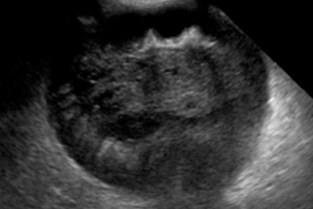

Le thème sera consacré aux affections hépato biliaires du chien et du chat. Si les signes cliniques et l’interprétation de l’enzymologie hépatique nous sont familiers pour suspecter une affection hépato biliaire, nous nous heurtons souvent à des difficultés pour confirmer l’affection et ainsi à incertitudes sur le traitement et le suivi à mettre en place.

Hugues Gaillot